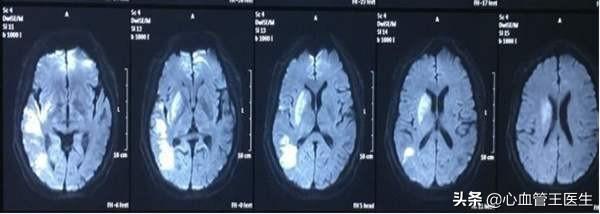

突然の左半身麻痺と失語症を呈した48歳の中年男性が、120番で救急外来に運ばれてきた。CTで大量の脳梗塞が示唆され、患者がカテーテル室に入った後、娘が泣いているように見えた。

入院時、患者の血圧は190/110mmHg、血糖値は13.7mmol/L、脂質コレステロールは7.5、LDLは5.3mmol/Lであり、典型的なトリプルハイであった。